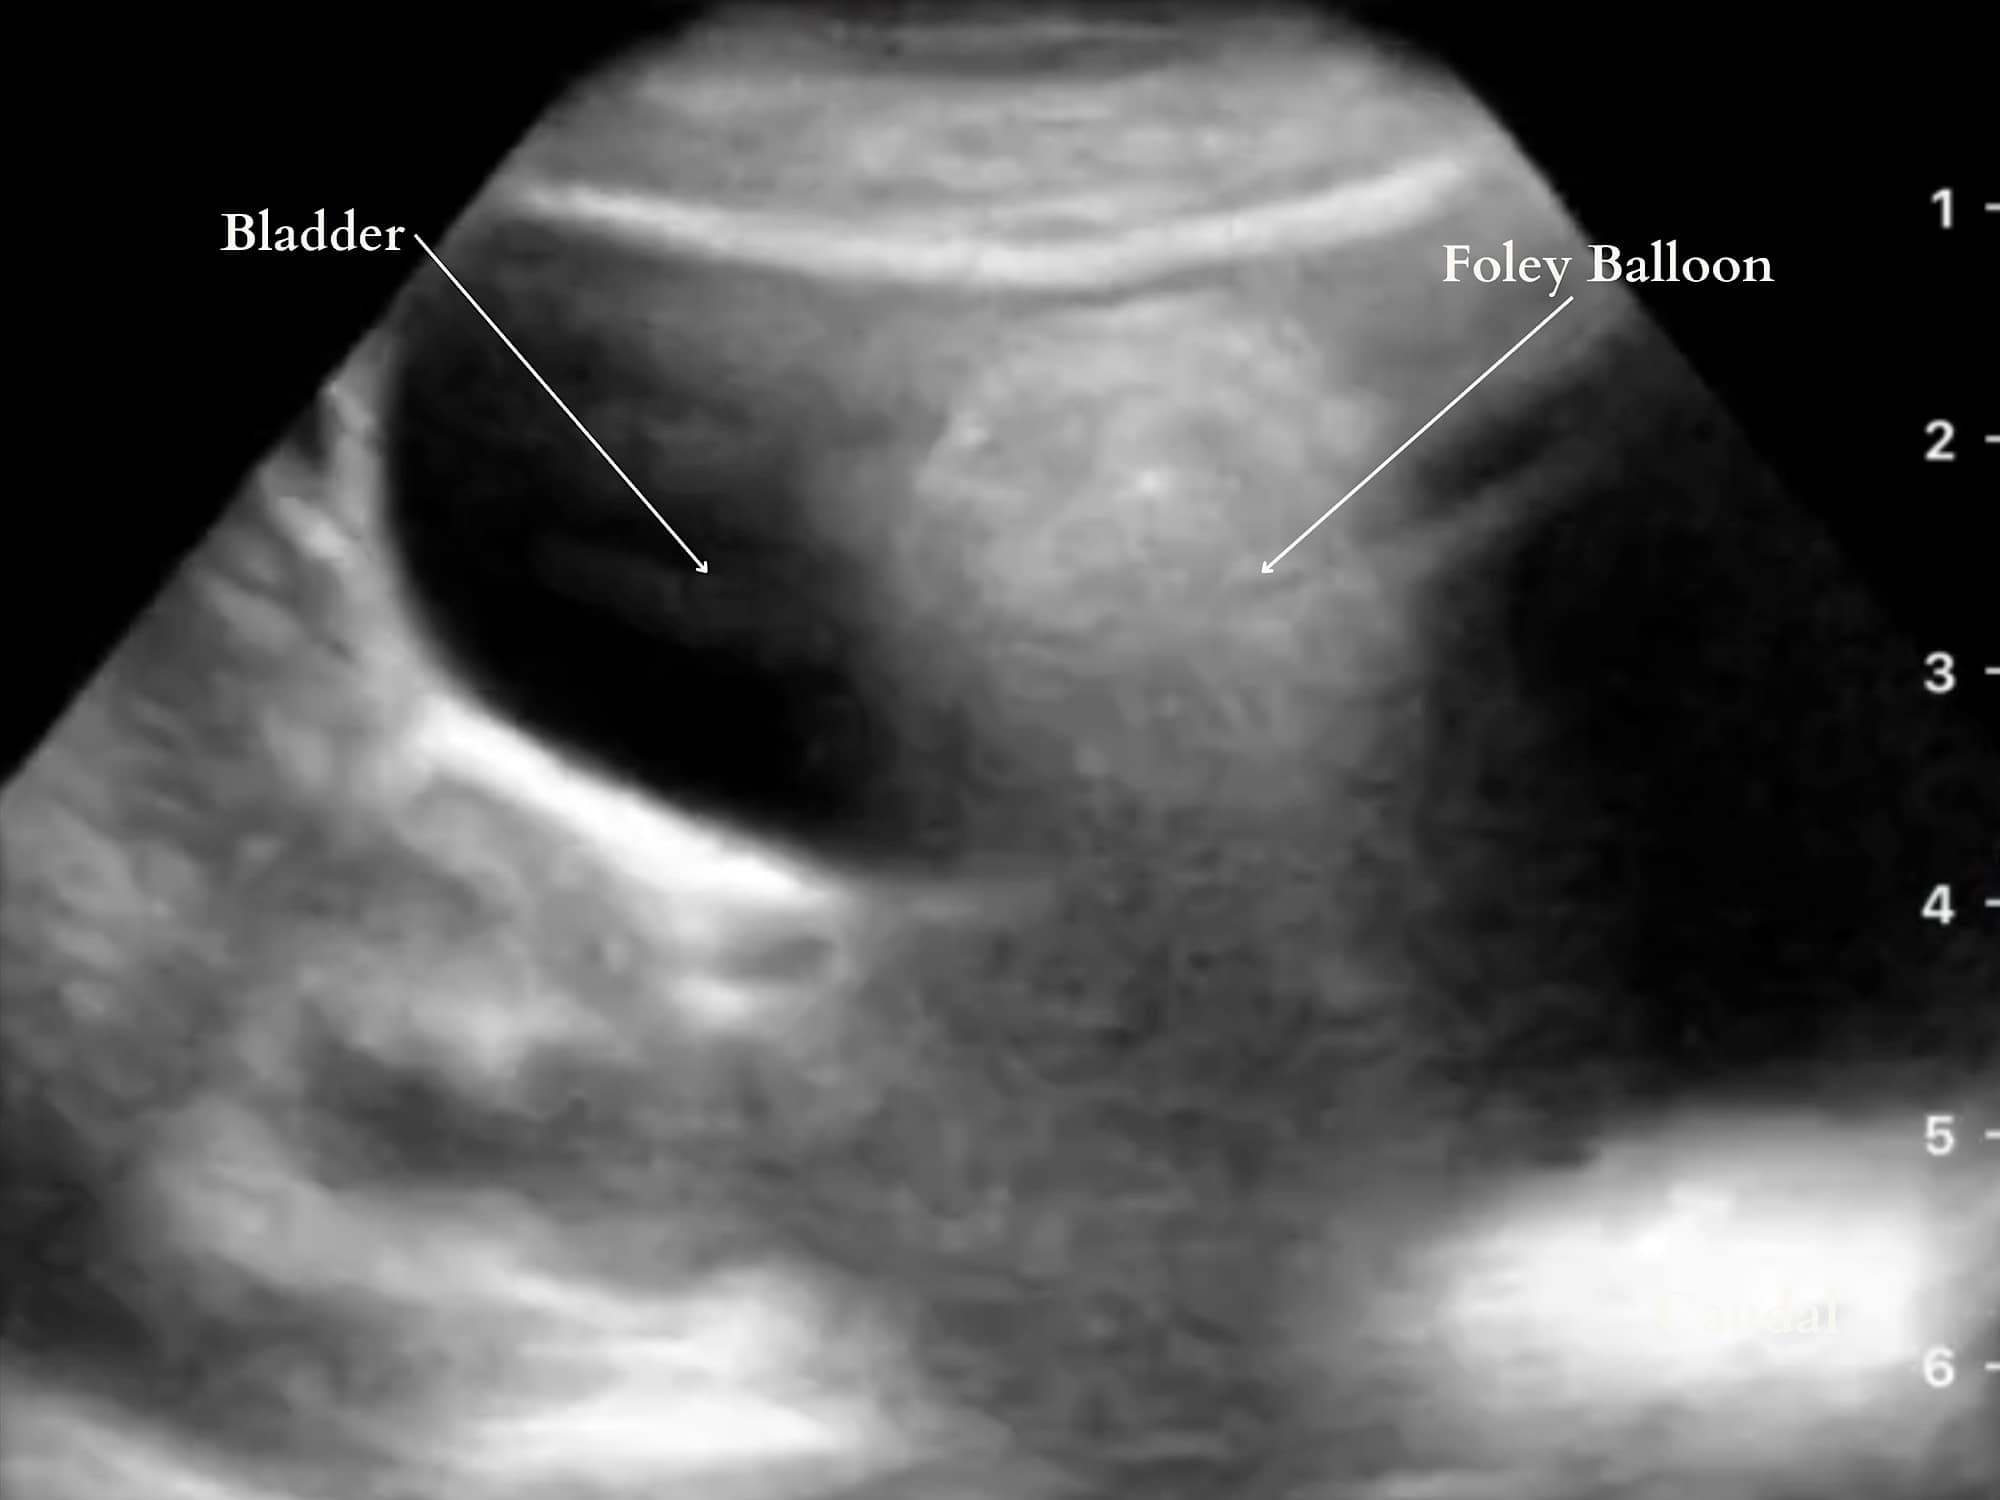

An interesting use of POCUS is for the visual confirmation of bladder or gastric tubes. There is minimal data specifically examining the use of ultrasonography for bladder catheter confirmation. However, difficulty with bladder catheter placement still occurs along with several injuries, such as inflating a balloon in the urethra in males.16 Ultrasonography can have the potential to verify or even troubleshoot placement.17 In one study, live transabdominal bladder scanning facilitated a challenging placement in an adult with transrectal pressure.18 Nasogastric tube placement confirmation is presented in the gastric ultrasound section. A Foley catheter is confirmed on a pelvic ultrasound scan. (Figure 8).

Reproduced with permission from baby-blocks.com